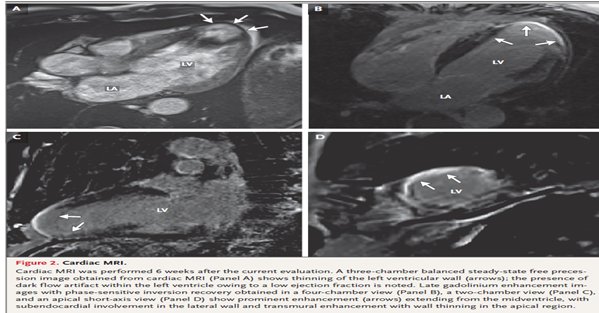

To Case 27-2025 από το Massachusetts General Hospital αφορούσε 53 χρονο με πολυεστιακά εμβολικά εγκεφαλικά(που συνηγορούν για καρδιακή και όχι αγγειακή προέλευση) από μη ισχαιμική μυοκαρδιοπάθεια(ΚΕ 28%) με ανεύρυσμα στη κορυφή και θρόμβο. Η διάγνωση ήταν ν. Chagas με αίτιο Trypanosoma cruzi. N Engl J Med 2025;393:1216-25. ESC 1225 In the PARACHUTE-HF study of patients with heart failure (HF) as result of Chagas disease, sacubitril/valsartan was superior to enalapril with respect to the primary endpoint of cardiovascular death, hospitalization for HF or the relative change from baseline to week 12 in NT-proBNP.